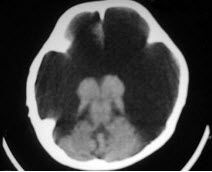

女,1岁半,头颅迅速增大,行CT检查如图,请选出最可能的诊断( )

A:积水型无脑畸形

B:硬膜外血肿

C:硬膜下血肿

D:硬膜下积液

E:脑内血肿